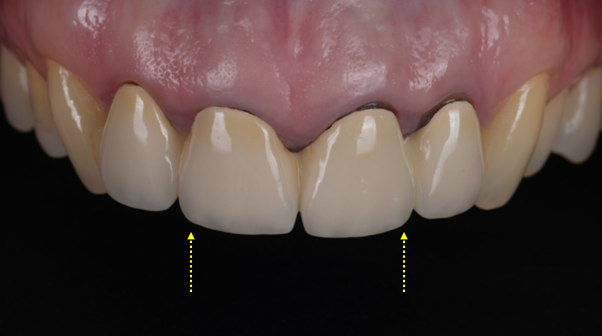

촬영 : 251030

최종적으로 완성된 지르코니아 크라운은 빛이 통과하면서 자연스러운 투명감이 느껴졌어요.

경계 부위가 검게 변해 있던 기존 모습이 생각나지 않을 정도로 큰 변화를 느낄 수 있었는데요.

환자분께서 거울을 보며 활짝 웃으셨던 순간이 아직도 기억납니다ㅎㅎ 개별 크라운으로 제작되어 치실 사용이 가능하여 사용법도 알려드렸습니다.

틀어진 치아 축도 얼굴 앞면을 바라보도록 제작했죠.